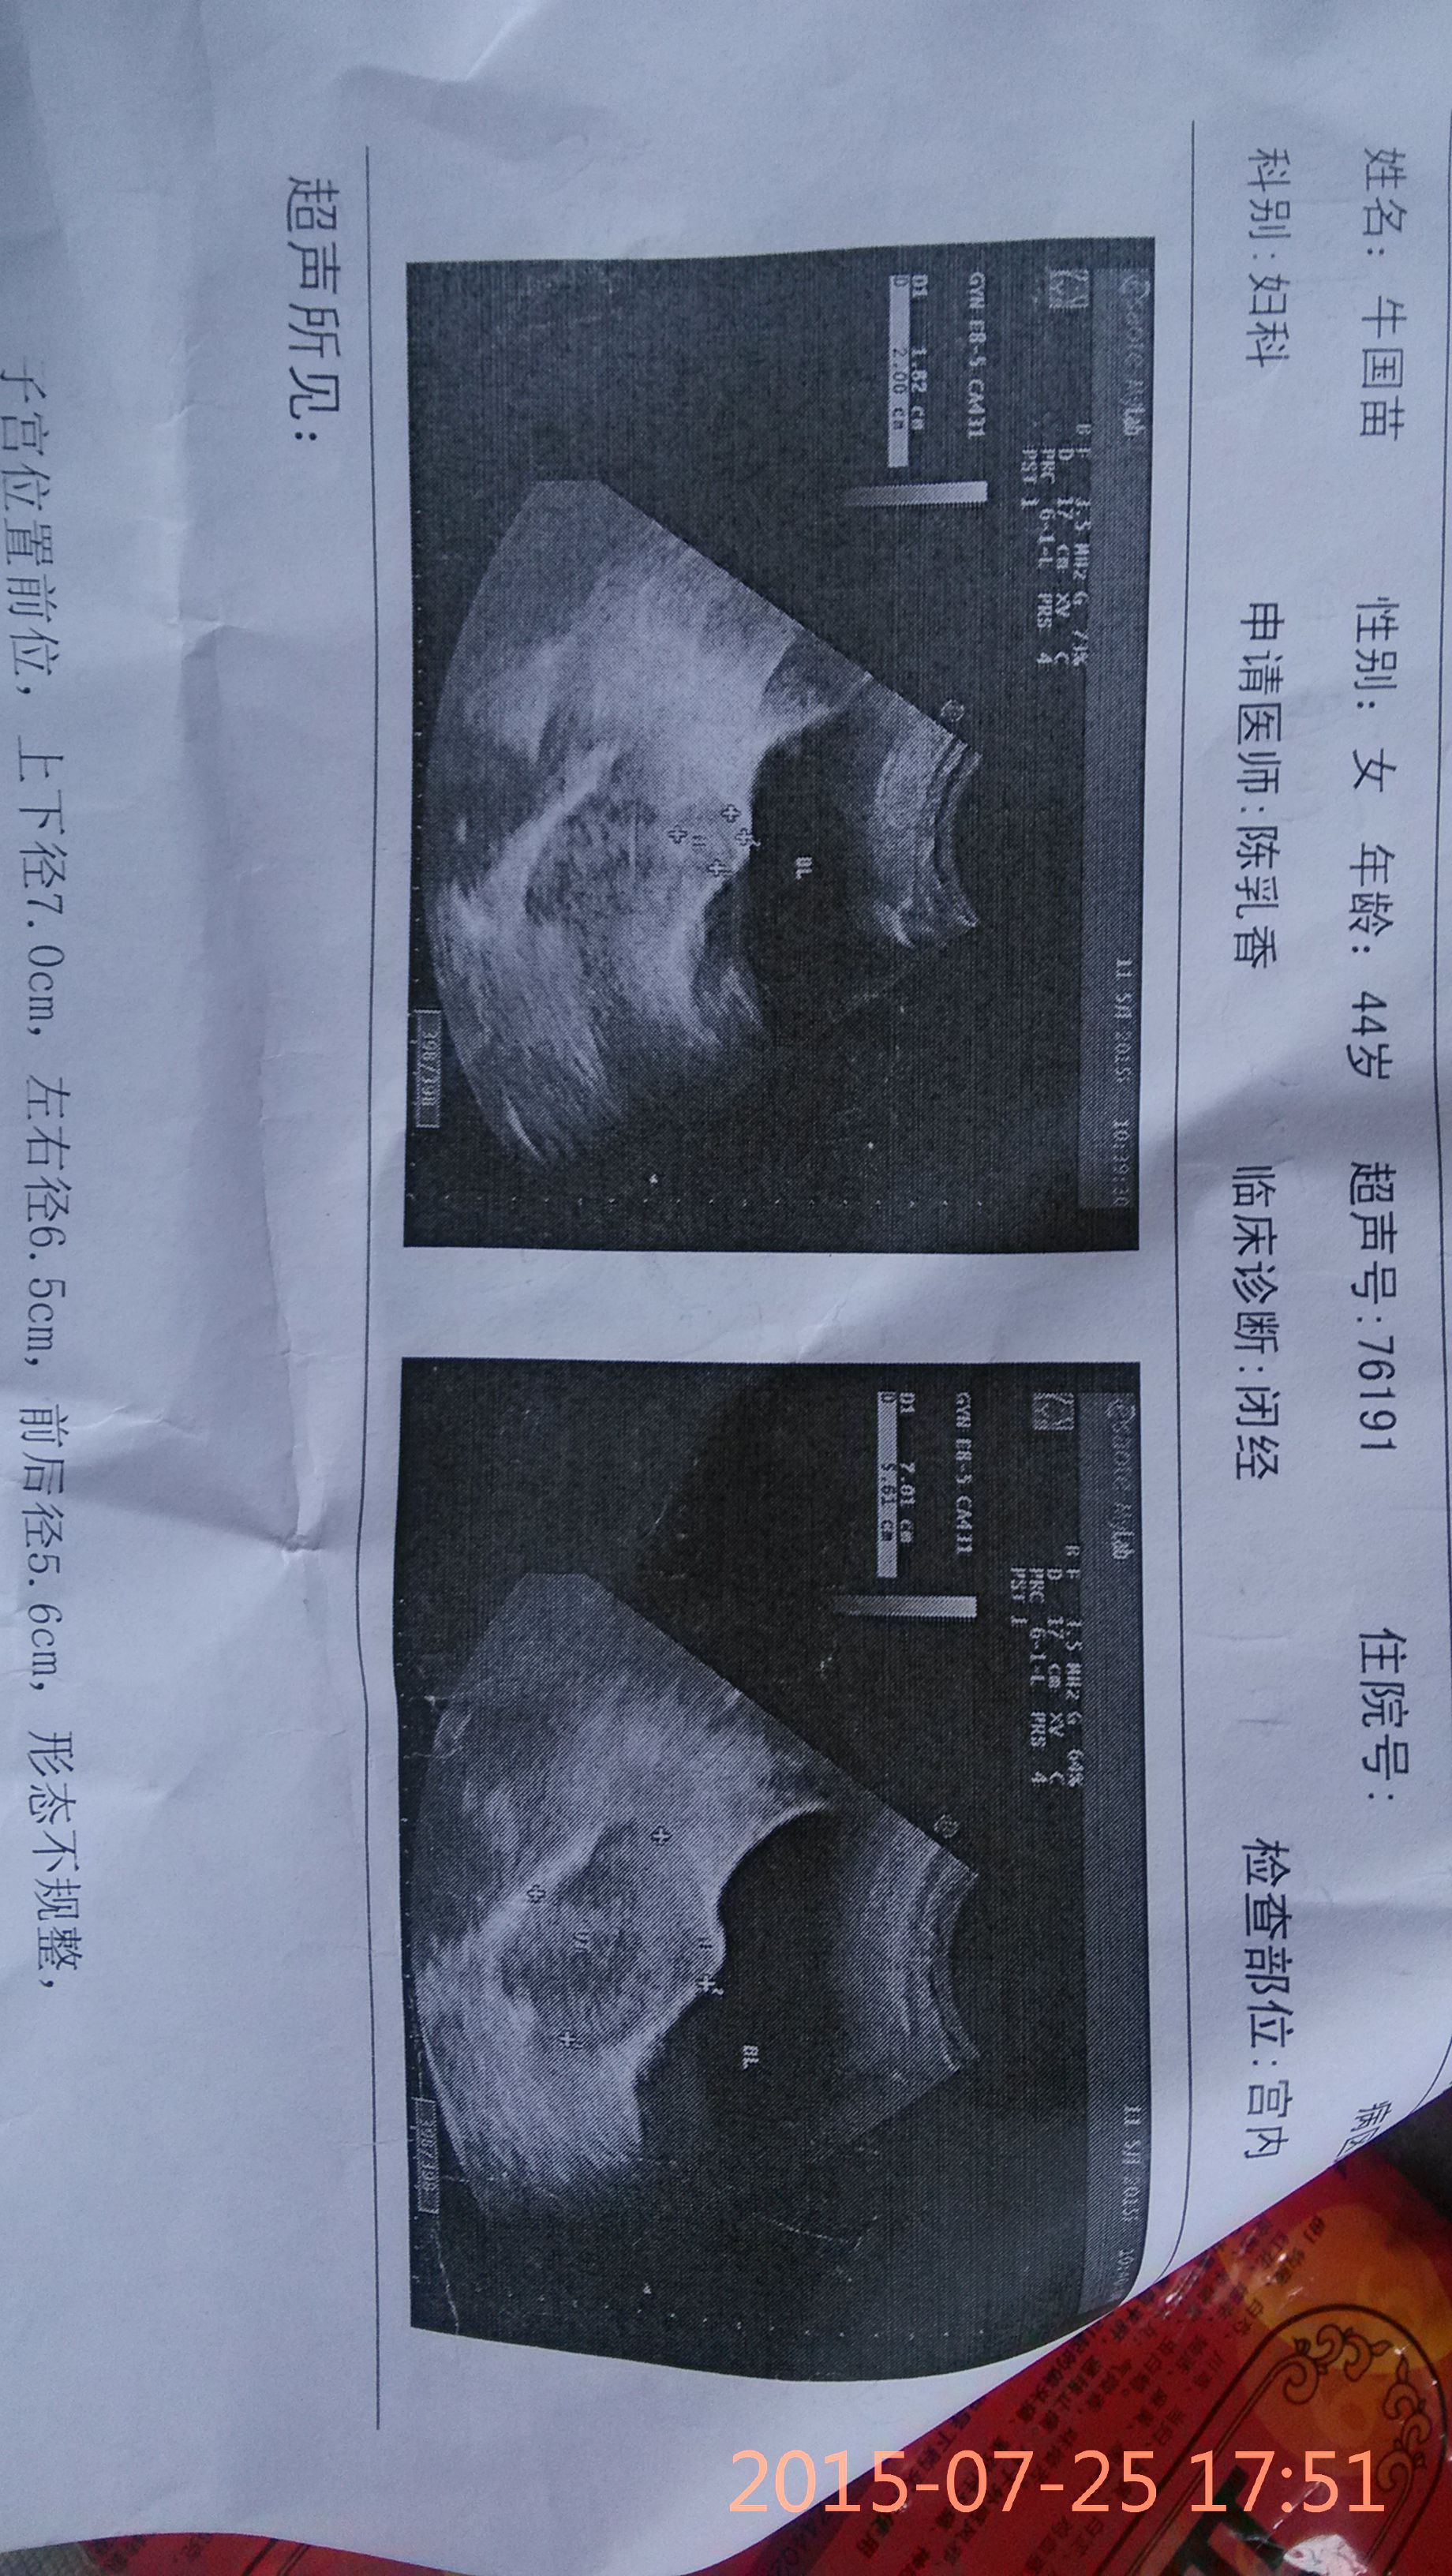

医生帮我看一下这个子宫肌瘤严重不严重 需不需要做手术 拜托了[图片][图片]3 点击展开 匿名用户 2015-07-25 18:44 满意回答 你好,你的肌瘤不大,如果是没有临床症状 那可以劳梅在医生的指导下采取药物进行保守治疗告宝告并注意定期复查查看菠金肌瘤的生长情况,如果生长不快那就可以继续保守治疗观察 ryn39 2015-07-25 18:46 宝宝知道提示您:回答为网友贡献,仅供参考。 相关问题 子宫肌瘤长在子宫外并且已经有7cm左右需不需要进行手术治疗 而且还是多发性的 我妈今年36周岁,她的子宫肌瘤是3 2*2 1求助需要禁忌哪些,严不严重 需要不需要手术,有什么更好治疗方法 鸭蛋配蜈蚣吃能治疗子宫肌瘤吗拜托各位了 3Q